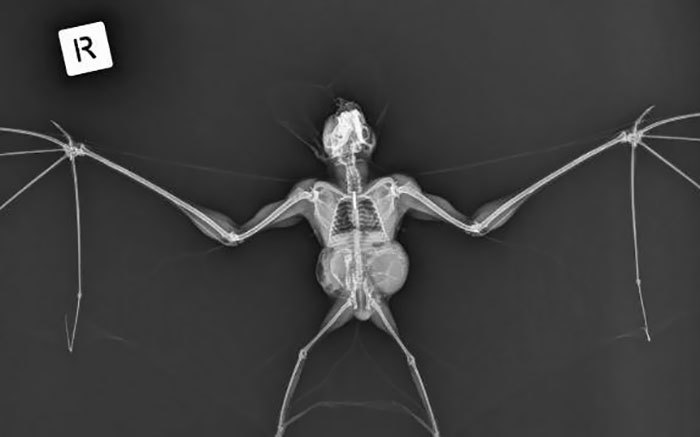

文章插图

幽灵蝙蝠的X射线